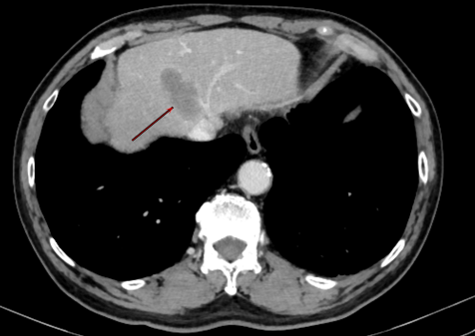

△腹部CT示肝转移瘤

“综合各项检查评估,目前考虑为肺癌肝转移,但值得庆幸的是,暂没有发现其他器官有转移,只有肝脏上面有一个转移病灶,位于肝脏S8段,这就有了手术切除的可能。”汪国营主任提出,患者安全是首位,必须要在保证肿瘤完整切除的同时,避免大出血,将手术风险降至最低,“因为肿瘤紧贴血管,并且患者有多年抽烟史,合并慢性阻塞性肺疾病10多年,是非常明显的桶状胸。”